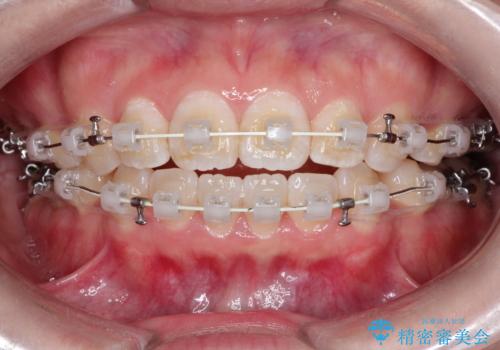

- 矯正装置

- 審美装置

- 治療期間

- 1年10ヶ月